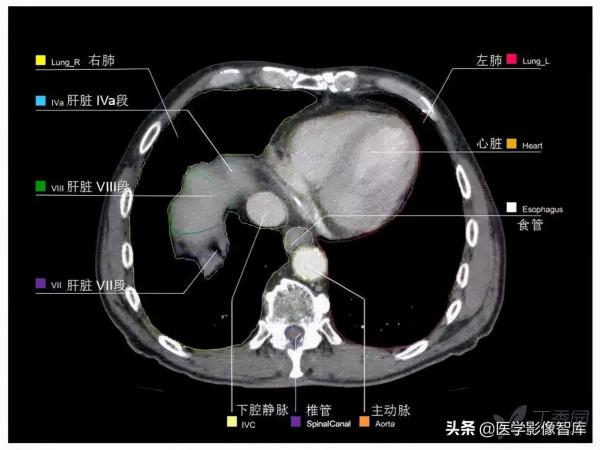

第十四層:肝靜脈水平

1. Intercostal muscle 肋間肌

2. Rib 肋骨

3. External oblique muscle 腹外肌

4. Right hepatic vein 肝右靜脈

5. Inferior vena cava 下腔靜脈

6. Left hepatic vein 肝左靜脈

7. Diaphragm 膈肌

8. Vagus nerve 迷走神經

9. Esophagus 食管

10. Liver (left lobe) 肝左葉

11. Rectus abdominis muscle 腹直肌

12. Stomach 胃

13. Left lung 左肺

14. Latissimus dorsi muscle 背闊肌

15. Liver (right lobe) 肝右葉

16. Right lung 右肺

17. Sympathetic trunk 交感幹

18. Erector spinae muscle 豎脊肌

19. Azygos vein 奇靜脈

20. Thoracic duct 胸導管

21. Spinal cord 脊髓

22. Thoracic vertebra 胸椎

23. Descending aorta 降主動脈

24. Posterior vagal trunk 迷走神經後幹

25. Spleen 脾臟